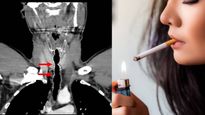

సిగరెట్ తాగడం వల్ల గొంతులో విపరీతంగా పెరిగిన వెంట్రుకలు..! అతని గతం తెలిస్తే షాక్ కావాల్సిందే..!